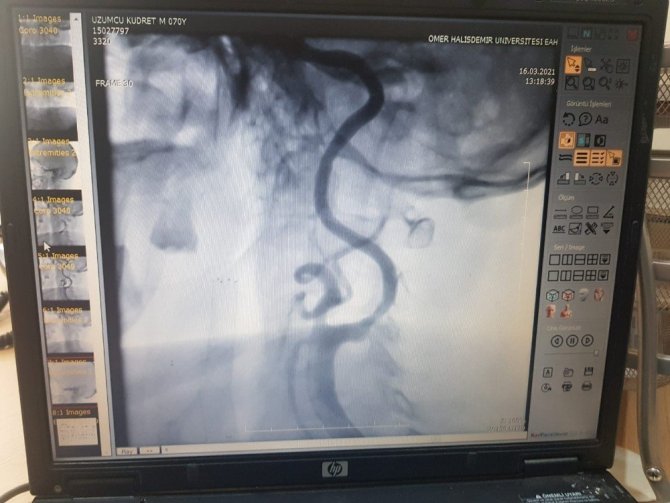

Yapılan muayenede, sol beyin damarının kapalı olduğu anlaşılan hasta, operasyona alındı.

Hastanın kapalı damarı, kardiyoloji uzmanı Yakup Çetinkaya, radyoloji uzmanı Halit Can Batur ve nöroloji uzmanı Halil İbrahim Akçay'ın kapalı anjiyo yöntemiyle stent yerleştirildi ve balonlama yöntemiyle açıldı.

Çetinkaya: ""Kalp damarlarını açtık ama daha önceden beyin damarlarına müdahale yapılmamıştı. Bu tür hastaların hepsi büyük şehirlere sevk ediliyordu. Kudret amcanın daha önce sağ beyin damarına Kayseri'de müdahale edilmişti. Sol damarına da planlanmış ama salgın nedeniyle müdahale yapılamamış. Biz de bu hastayı sevk etmeden burada tedavi ederiz diye düşündük, Başhekim Bilal Günaydın beyin de destekleriyle. Hastanın sol beyin damarı kapalı yöntemle kasığından girerek işlem yaptık ve stent yerleştirdik ve açtık. Hastamız da herhangi bir sıkıntı yok, taburcu ettik."